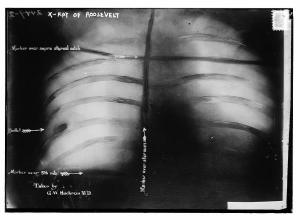

As Roosevelt was entering his car outside the Hotel Gilpatrick in Milwaukee, Schrank approached and fired a .38-caliber revolver. The bullet, rather than finding its mark directly, first passed through Roosevelt’s steel eyeglass case and the folded 50-page speech he had in his breast pocket, ultimately lodging in his chest.

Despite being shot, Roosevelt’s wound was not immediately fatal. The bullet had lodged in his chest muscle but did not penetrate the lung. The thick manuscript and eyeglass case had undeniably slowed the bullet, potentially saving his life.

Upon concluding his speech, Roosevelt was rushed to the hospital. Doctors assessed the wound and determined that it would be more dangerous to remove the bullet, which had lodged near his ribs, than to leave it. The bullet remained in Roosevelt’s chest for the rest of his life.